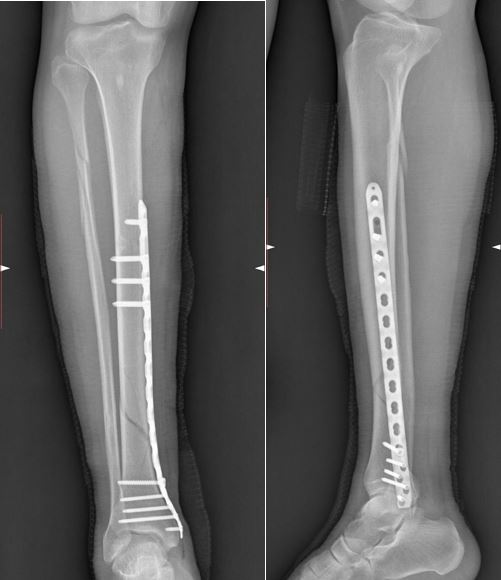

Интрамедуллярный остеосинтез (штифтование)

Золотой стандарт лечения переломов диафиза большеберцовой кости. В костно-мозговой канал большеберцовой кости вводится металлический штифт — стержень из медицинского сплава (чаще титан), который проходит через зону перелома и фиксируется блокирующими винтами выше и ниже перелома. Доступ минимальный — небольшой разрез у колена, основная работа выполняется через маленькие проколы под контролем ЭОП.

Преимущества: высокая механическая прочность, возможность ранней нагрузки, минимальная травматизация мягких тканей, низкий риск инфекции, хороший косметический результат.

Остеосинтез пластинами и винтами

Пластина — это металлическая конструкция, которая фиксируется к кости винтами вдоль её поверхности. Метод хорошо подходит для метаэпифизарных переломов (около суставов), внутрисуставных переломов, переломов мыщелков и дистального отдела (пилон, лодыжки). Современные анатомические предформованные пластины точно повторяют форму кости и обеспечивают стабильную фиксацию даже в сложных оскольчатых переломах.

Минимально инвазивный остеосинтез пластиной (MIPO) позволяет устанавливать пластину через небольшие разрезы без обнажения зоны перелома — это сохраняет кровоснабжение фрагментов и ускоряет сращение.